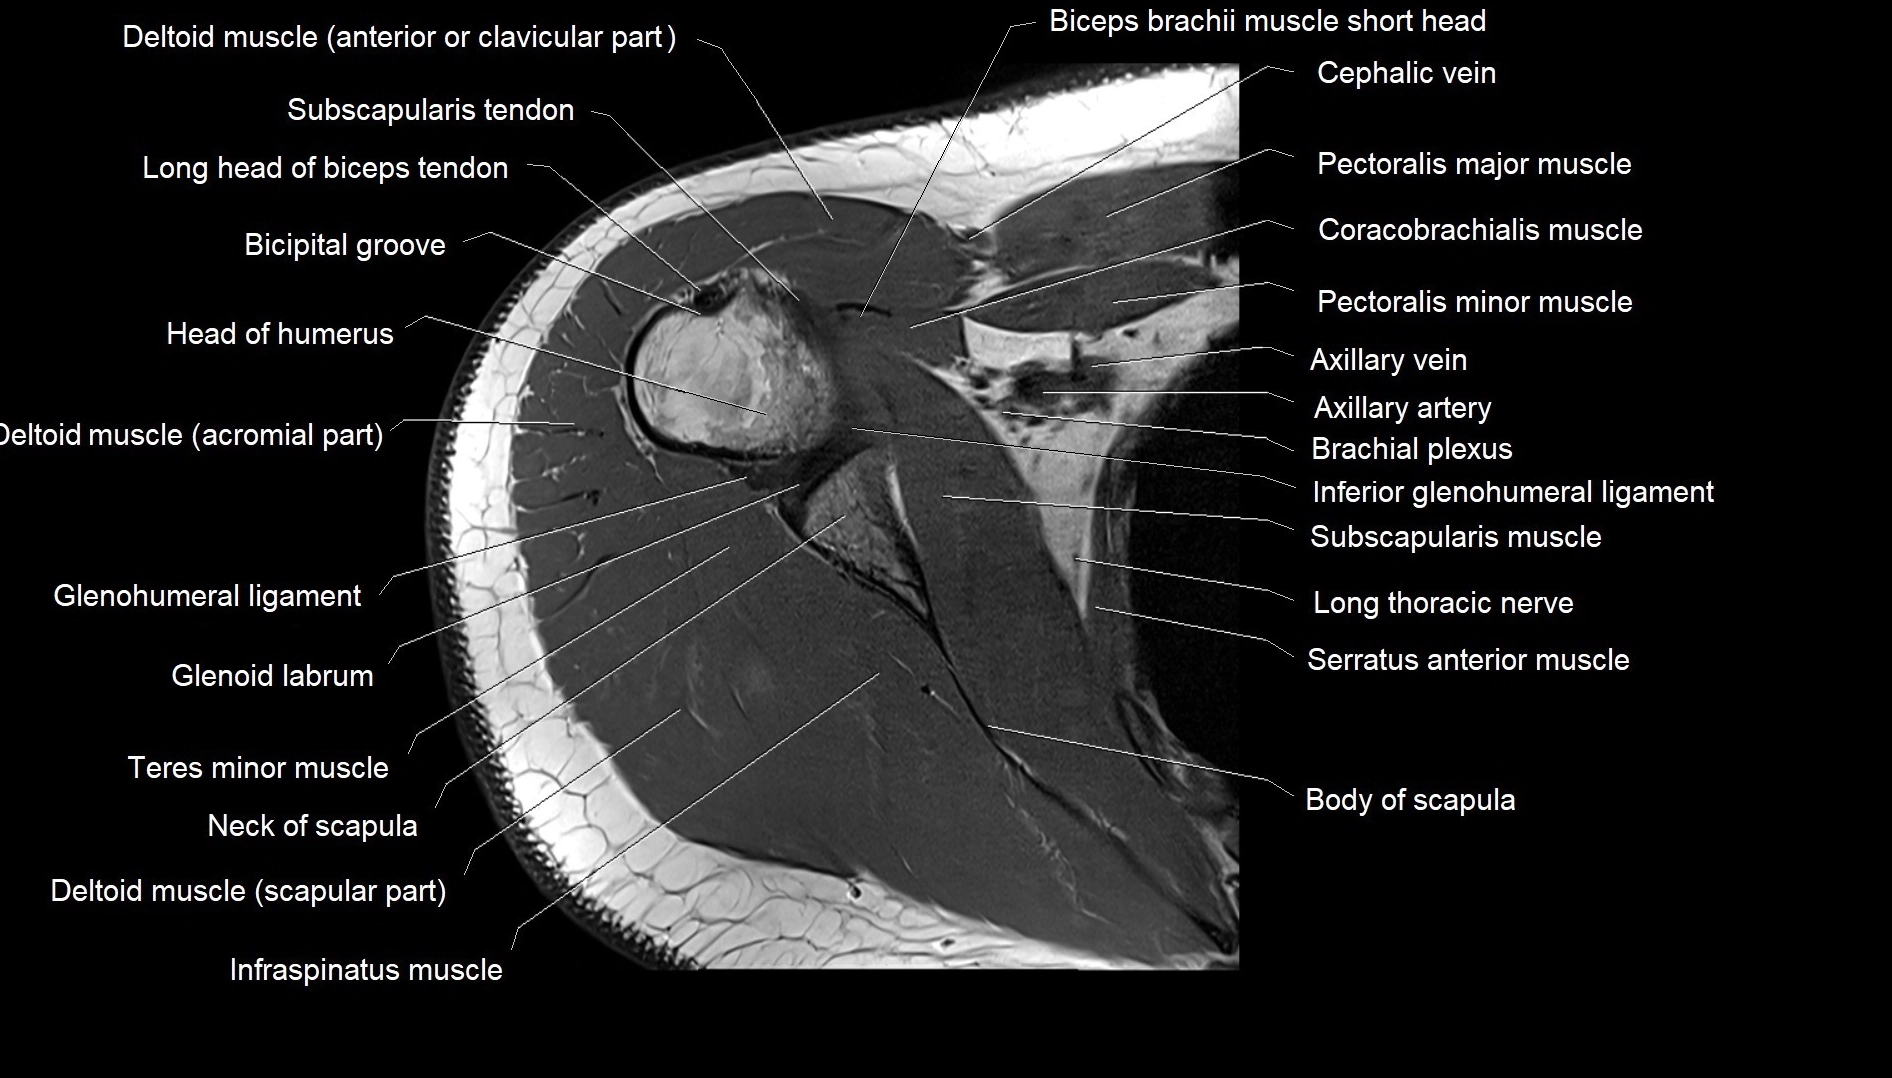

MRI images

image